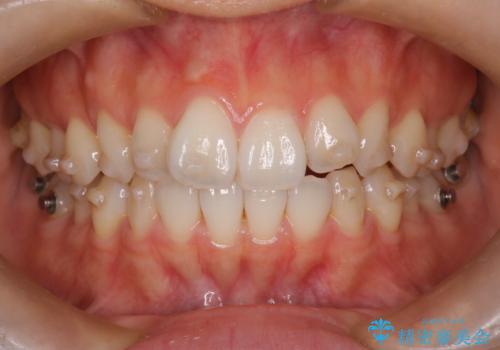

【インビザライン】前歯のねじれを治したい。

- 前歯の凸凹を主訴に来院されました。

スペースを作るために顎間ゴムを使用して、奥歯の遠心移動をおこない配列しました。

奥歯の遠心移動を行うことで、犬歯関係も良い状態に仕上げることができました。